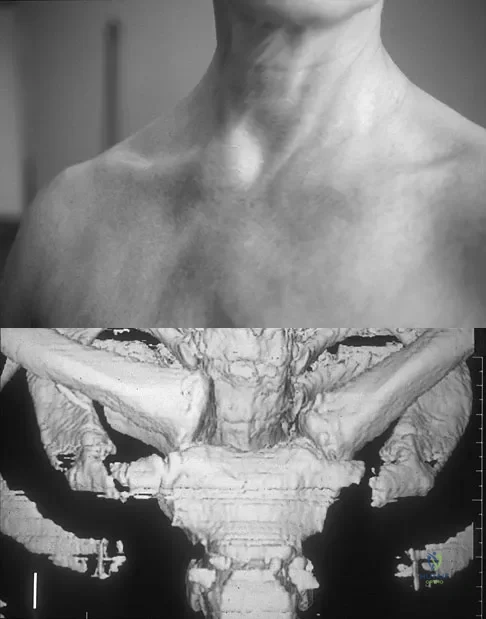

Question 63

Figure 11a shows the clinical photograph of a 46-year old woman who reports a 3-week history of pain and a "lump" at the base of her neck. She is otherwise in good health and denies any trauma. A 3-D reconstruction CT is shown in Figure 11b. What is the most likely diagnosis?

Explanation